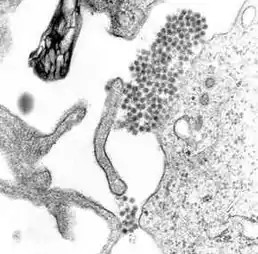

![]() Зображення з електронного мікроскопу збільшене у багато разів — вірус денге (скупчення темних цяток біля центру). | ||||||||||

Вірус денге належить до роду Flavivirus, родини Flaviviridae. До цієї родини також відносять інші віруси, які породжують захворювання у людей — жовтої гарячки, гарячки Західного Нілу, каліфорнійського енцефаліту, японського енцефаліту, кліщового енцефаліту, хвороби К'ясанурського лісу та омської геморагічної гарячки. Вони належать до екологічної групи арбовірусів — поширюються комахами.

Віруси денге мають РНК, двошарову ліпідну оболонку з фосфоліпідів і холестеролу, розміри віріона 40—45 нм в діаметрі. Інактивуються при обробці протеолітичними ферментами і при прогріванні вище 60 °C, ультрафіолетовим опромінюванням. Розмножуються на культурах тканин і клітинах нирок мавп, хом'яків тощо. У сироватці крові хворих вірус зберігається при кімнатній температурі до 2 міс., а висушений — до 5 років.